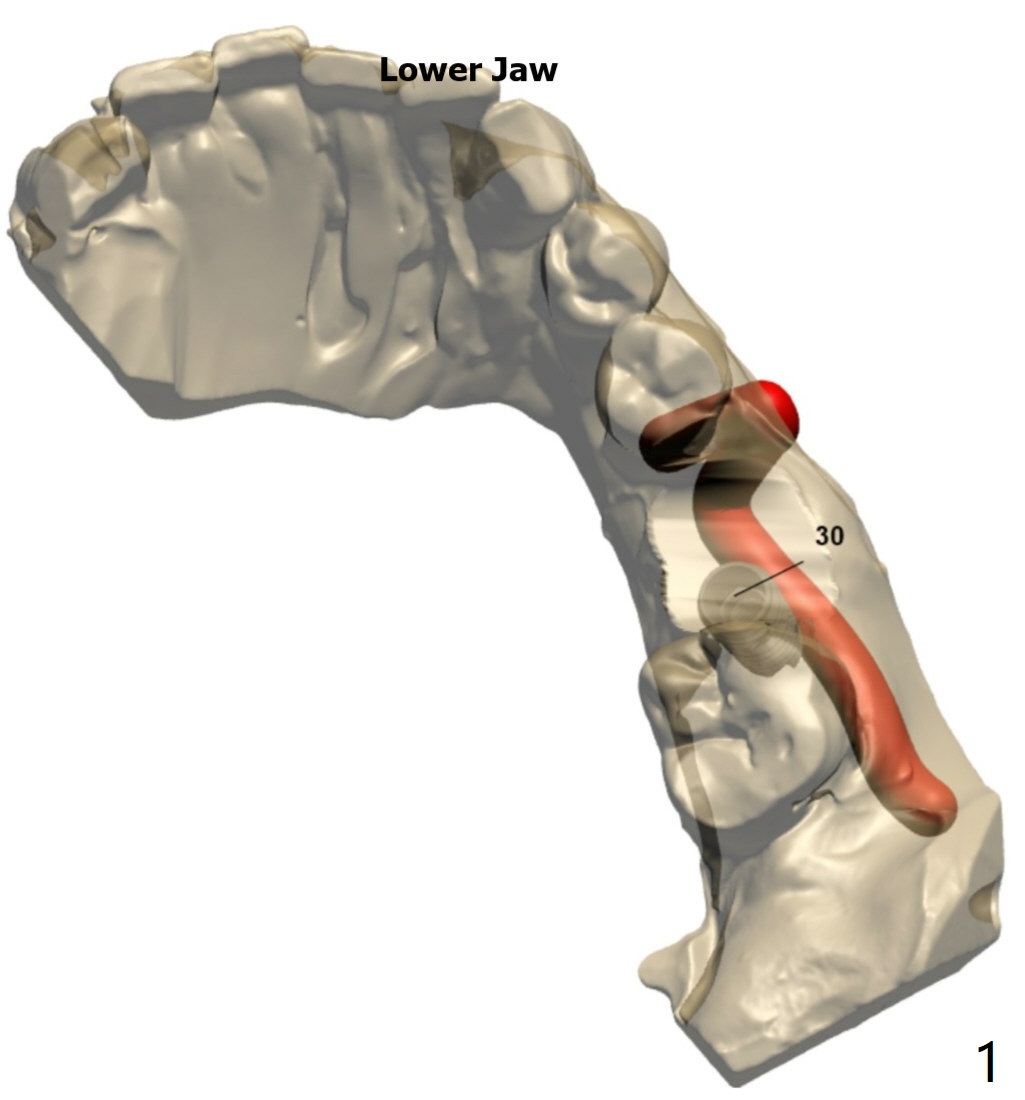

Branch of Inferior Alveolar Nerve